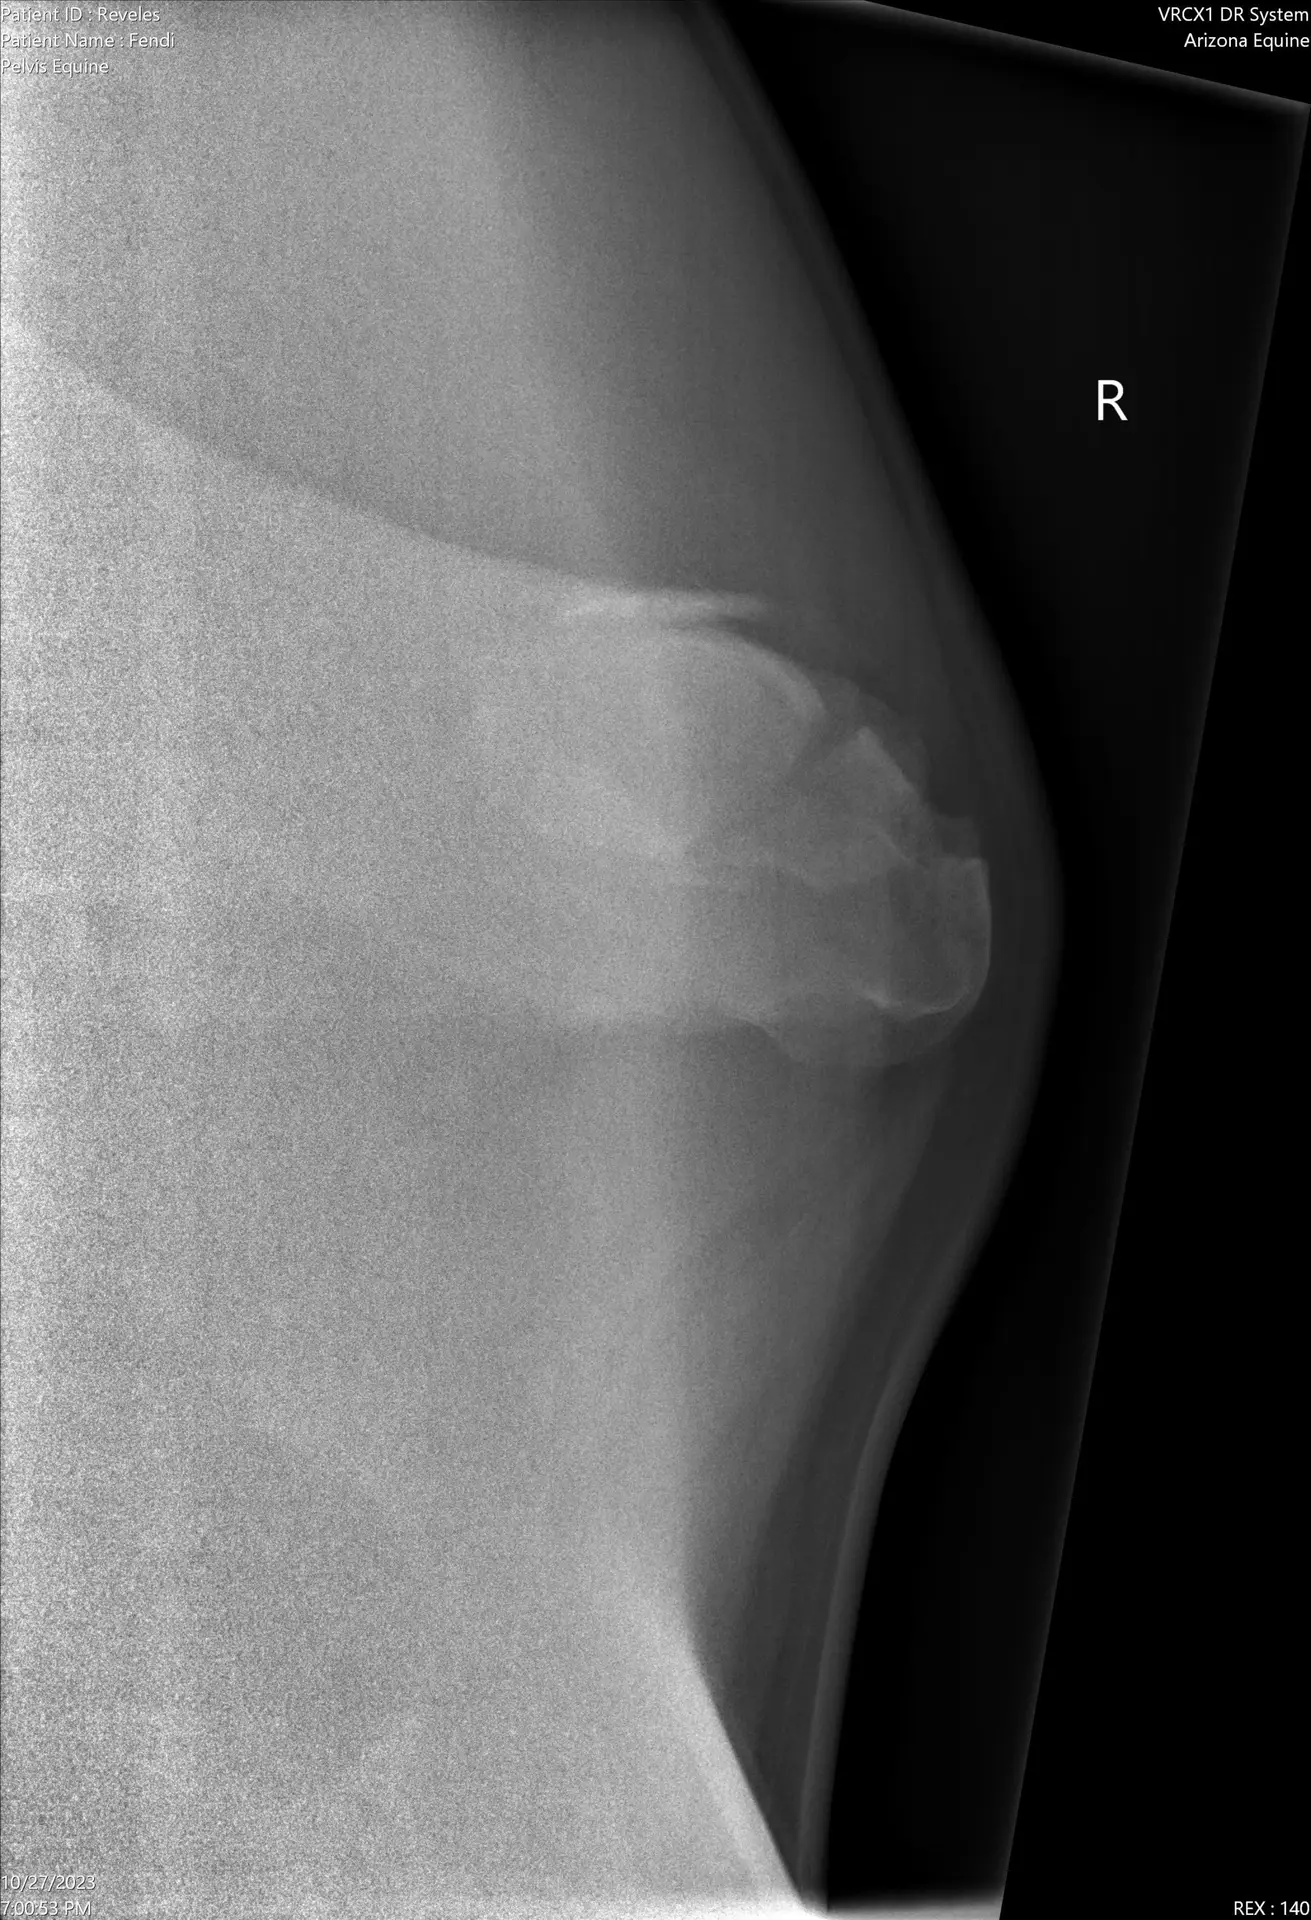

Fendi, a 6-year-old warmblood mare, sustained a right hind limb injury in mid-October 2023 when she ran into an object, causing a laceration over her right tuber coxae. She developed swelling, soreness, and remained 2/5 lame despite rest. A full-body bone scan on October 30, 2023, revealed an extreme focal hot spot at the right tuber coxae, and radiographs confirmed a mildly displaced comminuted fracture. She was placed on stall rest with a run to allow healing.

Fendi-20231027-DX_2